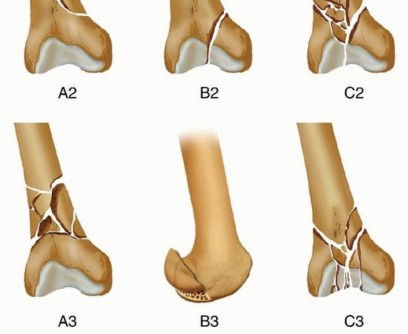

### FIG 7 • AP (A) and lateral (B) views of a three-dimensional (3-D) CT reconstruction of the patient in FIG 3B with a distal femur fracture. The fracture is well defined. C. An oblique 3-D CT reconstruction view showing the same patient and the rotational malalignment between condyles. ## SURGICAL MANAGEMENT 471 The goal of any treatment, nonoperative or operative, is to maintain or restore the congruity of the articular surface and restore the length and alignment of the femur and, subsequently, the limb. Once surgery is deemed appropriate for the patient and the particular injury, the surgical technique options available are determined by the particular fracture pattern. Distal femur fractures have been classified several ways. The OTA/AO classification is probably the most widely accepted classification system and allows some guidance on which techniques are best ( FIG 8; Table 1). Treatment also must be determined based on factors other than the classification alone. The degree of comminution and injury to both the articular surface and bone The amount of fracture displacement The soft tissue injury Associated injuries, other fractures, and injury to neurovascular structures

### FIG 8 • OTA/AO classification for distal femur fractures (types 33A, B, and C).*

OTA/AO Classification of Femoral Fractures

- Classification Description Type A Extra-articular A1 Simple or two-part fracture A2 Metaphyseal butterfly or wedge fracture A3 Metaphysis is comminuted Type B Partial articular B1 Sagittal plane fracture of the lateral femoral condyle B2 Sagittal plane fracture of the medial femoral condyle B3 Any frontal or coronal plane fracture of the condyle (Hoffa type) Type C Intra-articular C1 Simple articular split and metaphyseal injury (T or Y fracture configuration) C2 Simple articular split with comminuted metaphyseal injury C3 Comminuted articular with varying metaphyseal injury Patient's overall condition and injury to other organ systems. This may affect the timing of surgery or the positioning of the patient. There are several principles for the surgical management of distal femur fractures. The articular surface must be reduced anatomically, which usually requires direct visualization through an open exposure (arthrotomy). Simple intra-articular splits may be treated with closed reduction and percutaneous fixation. The extra-articular injury should be dealt with using indirect reduction techniques as much as possible to maintain a biologic soft tissue envelope. Avoidance of stripping of the tissues, especially on the medial side, is ideal. The surgeon must reestablish the length, rotation, and alignment of the femur and the limb. The soft tissue injury and bone quality may dictate treatment decisions. ## Fixation Choices External fixation A temporary bridging external fixator across the knee joint can be used if temporary stabilization is required before definitive fixation. This is usually the case where definitive open reduction and internal fixation (ORIF) is planned. This could be in cases where the soft tissues prevent immediate fixation. Definitive management with bridging or nonbridging external fixation can be used for nonreconstructible joints, very severe soft tissue injuries, or severe osteopenia. Bridging external fixation can be used when definitive ORIF is problematic in certain patient populations, such as Jehovah's witnesses, where additional blood loss can lead to increased morbidity or mortality. This can be done temporarily until the patient's condition improves or until healing ( FIG 9). Intramedullary nailing This can be performed fairly acutely; temporary bridging external fixation is not necessary. 472